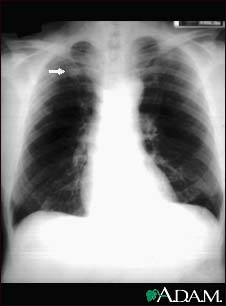

Pulmonary nodule - front view chest X-ray

This x-ray shows a single lesion (pulmonary nodule) in the upper right lung (seen as a light area on the left side of the picture). The nodule has distinct borders (well-defined) and is uniform in density. Tuberculosis (TB) and other diseases can cause this type of lesion.